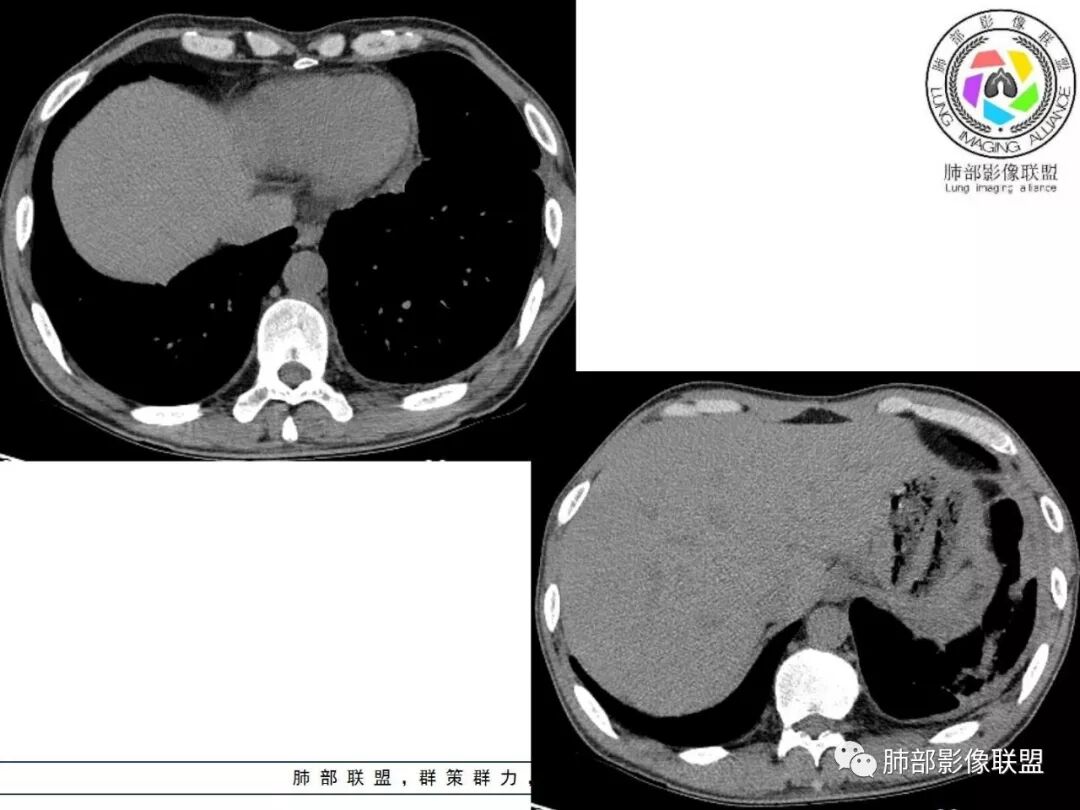

胸部CT:两肺弥漫病灶,磨玻璃影,少许实变,部分累及胸膜,磨玻璃区可见囊?少许胸腔积液,两肺可见结节,支气管血管束增粗,小叶间隔增厚,支气管走形有扭曲扩张,可见纤维化。气肿、大泡。考虑:感染性病变,PCP?查下HIV,CD4,G等。鉴别结核、结缔组织病肺浸润。

临床看,首先考虑感染性病变,特异性感染可能大,病毒直接pass掉,真菌和结核选一个。基础病变是肺气肿,不能看成蜂窝征。肺门淋巴结有钙化趋势,午后低热。心包胸腔都有少量积液。病变渗出和实变并存。结核

中年男性,中等病程,发热待诊,体温可高达40度,超敏c升高,pct升高,白细胞不高,血沉不高,双肺多发弥漫性病灶,间质性改变,胸膜增厚,心包积液,考虑感染性疾病,结核?诺卡?鉴别pcp,op。

从内科的角度一点不意外,而且病史采集很到位,午后低热,同时出现心包和胸腔积液,常见病中,最可能是结核和转移。前面说过,其他一些征象也支持结核。

弥漫性间质疾病,还伴心包,胸腔积液的,肺水肿也有可能,但临床不符,没有胸闷气急。

1.  老年男性,发热为主诉,体温38°-39°,发热以午后及晚上为主,伴黄痰,CRP增高,临床病史支持感染性病变;

2. 肺气肿背景(小叶中心性肺气肿);双肺多发病灶整体沿血管支气管束及胸膜下分布,以上叶及下叶背段分布为主,有实变及GGO,边界清楚,有树芽,小叶间隔及中央间质增厚,叶间裂见到多发结节,部分支气管不规则牵拉扩张,提示病灶纤维化明显,结合临床病史,考虑病灶为间质性感染,肺门及纵隔内有钙化淋巴结,小叶间隔结节,考虑淋巴道增值性疾病可能,综合常规要怀疑间质性肺结核。